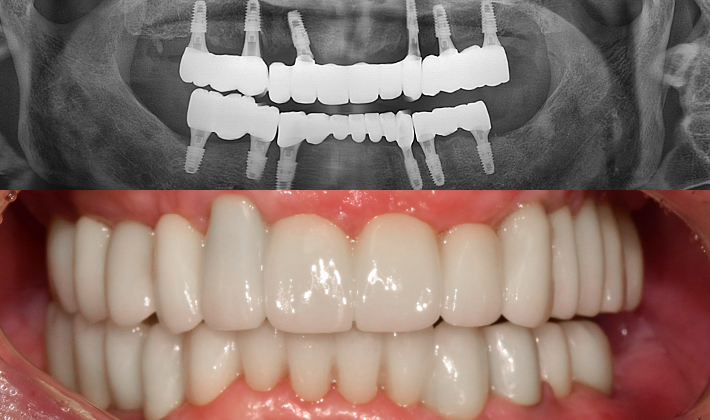

실제 치료 사례

수많은 환자들이 고민 끝에 선택한 치료,

그리고 그 후의 놀라운 변화

- ※ 위 임상사진은 365서울원탑치과에서 진료를 시작하고 마친 동일한 환자의 사진입니다.

- ※ 위 임상사진은 동일한 장소에서 동일한 조건으로 촬영되었으며, 사진에 대한 별도의 조작이 처리되지 않았습니다.

- ※ 수술 및 치료 과정에서 부작용이 발생할 수 있으므로 의료진과의 충분한 상담과 신중한 판단이 요구됩니다.

환자를 향한 진심,

완성도 높은 결과

환자의 상태를 세심하게 살피고,

글로벌 스탠다드에

맞춘

진단과

치료 과정을 통해 보다 안전하고

완성도

높은 결과를 만듭니다.